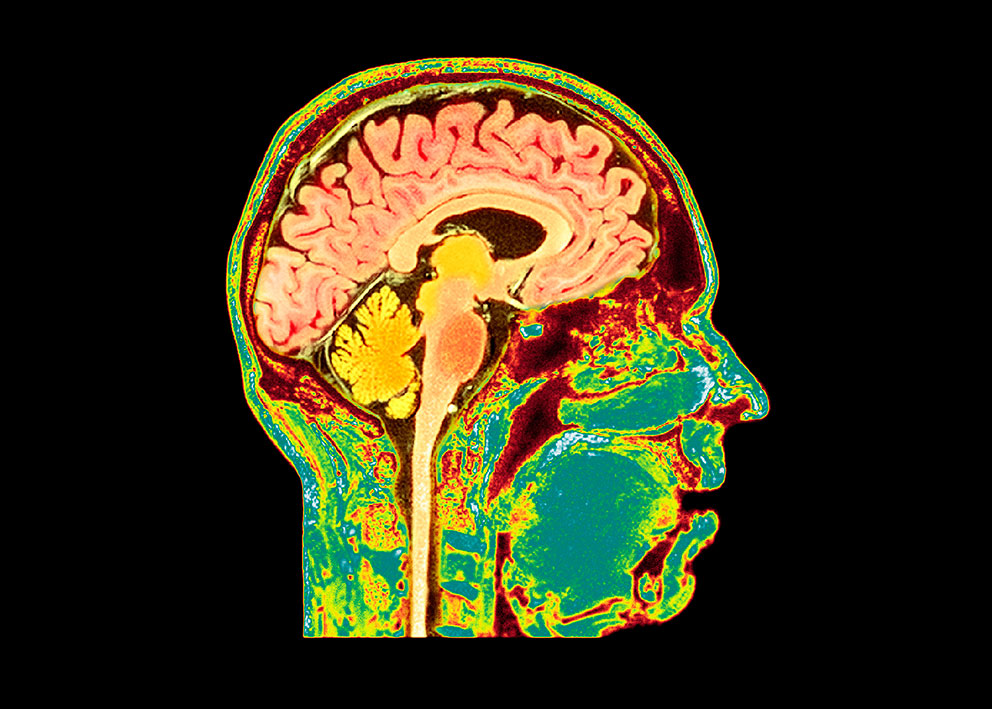

Foto: Science Photo Library / NTB

Kakeksi, som kan ses ved langtkommen kreft, kjennetegnes av tap av vekt, fett og muskelmasse, samt symptomer som utmattelse og dårlig matlyst. Pasienten er gjerne deprimert og apatisk. En ny musestudie publisert i tidsskriftet Science, har kartlagt en nevroimmun signalsløyfe som ligger bak apati ved kakeksi, utløst av injeksjoner med kreftceller (1).

Injeksjonen av kreftceller utløste en systemisk inflammasjon og ga økte nivåer av sirkulerende cytokiner. En omfattende screening viste at nivået av interleukin-6 i blodet endret seg parallelt med en progresjon av kakeksien. Avanserte nevrofysiologiske metoder viste at en cerebral signalsløyfe som signalerer kakeksi, startet i hjernens area postrema, som er et hjerneavsnitt spesialisert til å detektere blodbårne signaler, blant annet interleukin-6. Signalsløyfen førte til nedsatt dopamindannelse, noe som økte følsomheten for anstrengelser og dermed utløste apatiliknende oppførsel hos musene. Antistoff mot interleukin-6 slo ut cytokinsansingen i hjernestammen eller den medikamentelt stimulerte dopaminproduksjonen. Apati ved kakeksi trenger altså ikke være en sekundær effekt av fysisk svekkelse, men kan oppstå gjennom samme mekanisme som selve kakeksien. Selv om signalsløyfen stimulerer hensiktsmessig oppførsel under akutt sykdom ved å konservere energi og dempe motivasjonen for handling, er den uheldig ved kroniske tilstander som kakeksi.